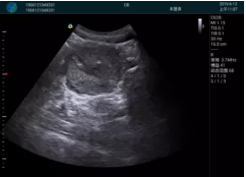

甲狀腺囊性結(jié)節(jié),囊壁鈣化,透聲好

甲狀腺囊性占位